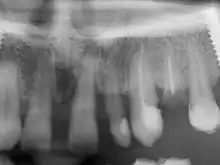

Pe baza unei radiografii panoramice se poate evalua gradul de pierdere osoasă acesta fiind de fapt indicatorul scaderii calitatii colagenului din osul maxilar sub actiunea diversilor factori inflamatori (retentie alimentara sub retentii determinate de coroane ceramice si implante dentare).